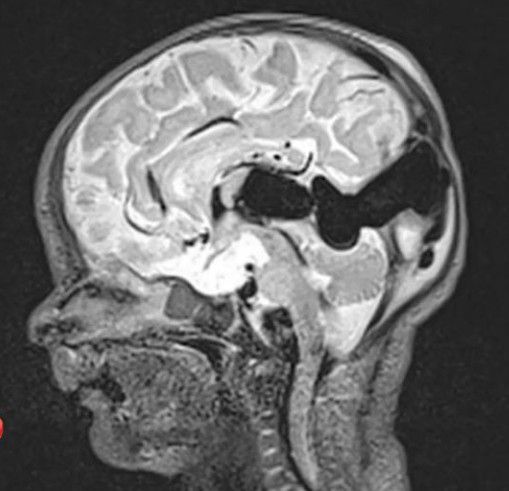

✅It is constituted by a midline dilated venous structure that receives blood from abnormal macroscopic or microscopic arteriovenous shunting vessels.⠀ ⠀ ✅Between the 6th and the 11th wk of intrauterine life, the arterial supply to the forming telencephalic choroidal plexus comes from the primary terminal branches of the internal carotid artery, while the venous drainage is directed toward the median prosencephalic vein.⠀ ⠀ ⠀ ✅This vessel than regresses and form the two internal cerebral veins and, in its most caudal part, the vein of Galen. ⠀ ⠀ ⠀ ✅🔷The failure of the regression of the median prosencephalic vein causes the formation of direct arteriovenous fistulae within the velum interpositum and the quadrigeminal cistern, where the vein is located.⠀ ⠀ ✅The median prosencephalic vein dilates and may reach a balloon size and the high flow into the fistula does not allow the normal dural sinuses to form⠀ ⠀ ⏩It is of two types, choroidal and mural. ⠀ ⠀ ✅Choroidal is seen in most neonates with a low clinical score, because of cardiac failure.⠀ ⠀ 🔷It is supplied from all choroidal arteries and their branches that open into the enlarged venous pouch.⠀ ⠀ ✅Mural is better tolerated and is seen in infants without cardiac symptoms. It is formed from single or multiple direct AV fistulae within the wall of it.⠀ ⠀ ⏩The cardiac manifestations can range from asymptomatic cardiomegaly to severe congestive cardiac failure.⠀ ⠀ ✅This rapidly progressive disease worsens within the first three days of life.⠀ ⠀ 🔷The medical treatment is based on low dose inotropic support and peripheral vasodilatation that improve the cardiac output.⠀ ⠀ 🔷CCF resolves spontaneously after a proper endovascular treatment. By: https://www.instagram.com/p/CZPBCEkhsKN/?utm_source=ig_web_copy_link